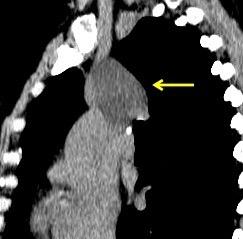

“Draped aorta”.

Indica rotura aórtica reciente. Se manifiesta por una pared aórtica posterior o el contacto con el borde lateral vertebral borrados por la hemorragia.

Rotura aneurisma de Aorta descendente.

Dolor. (10 días antes: "Rotura inminente”)